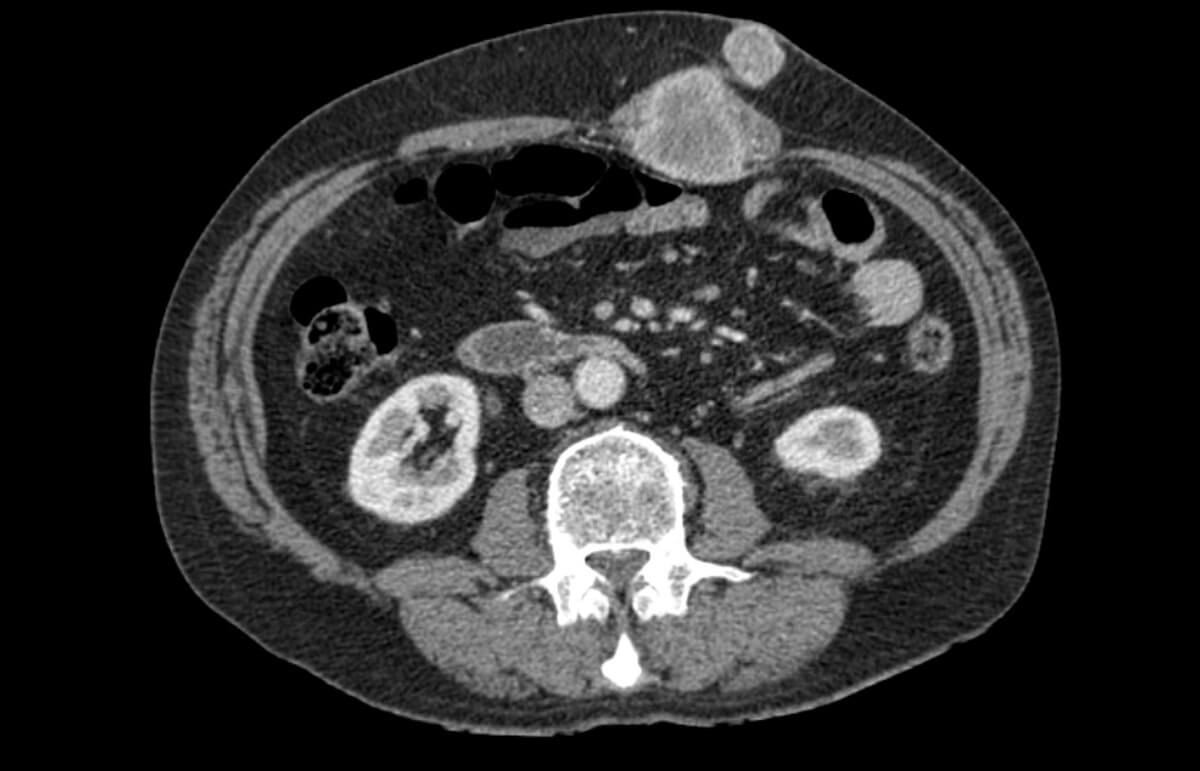

Figure 3: An axial CT image 18 months after surgery demonstrating two left-sided abdominal wall deposits.

The subsequent CT scan at 18 months demonstrated significant progression of these radiological changes (Figure 3). Two distinct contrast enhancing masses were visible - a 44mm lesion in the body of the left rectus muscle, and another 23mm in the adjacent subcutaneous tissue. The masses were excised with support from a general surgeon specialising in abdominal wall closure, and histology confirmed the suspicion of two metastatic renal cell carcinoma deposits.